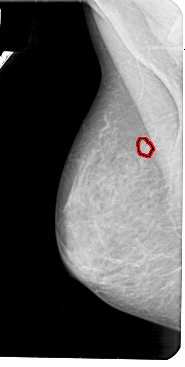

A_1947_1.LEFT_CC

LEFT_CC LINES 5356 PIXELS_PER_LINE 2806 BITS_PER_PIXEL 12 RESOLUTION 43.5 OVERLAY

FILE: A_1947_1.LEFT_MLO.OVERLAY

TOTAL_ABNORMALITIES 1

ABNORMALITY 1

LESION_TYPE MASS SHAPE ROUND MARGINS CIRCUMSCRIBED

ASSESSMENT 3

SUBTLETY 4

PATHOLOGY BENIGN

TOTAL_OUTLINES 1

BOUNDARY